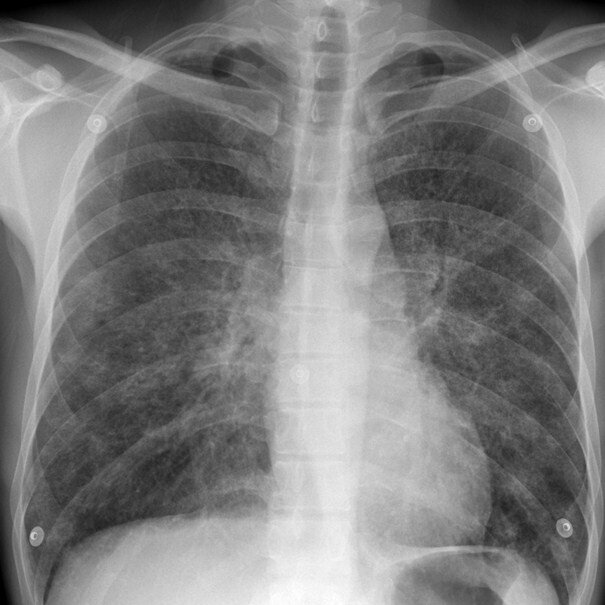

Диагноз ПНЕВМОНИЯ является определенным при наличии у пациента:

1) Рентгенологически подтвержденной очаговой инфильтрации легочной ткани и, по крайней мере, двух клинических симптомов и признаков из числа следующих: